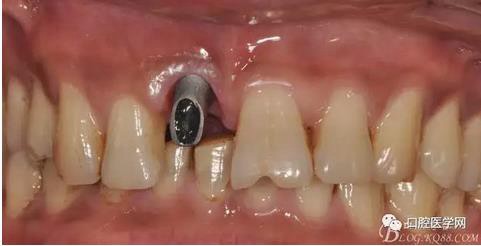

圖19 口內(nèi)修復(fù)基臺正位照

圖20 口內(nèi)修復(fù)基臺正位照